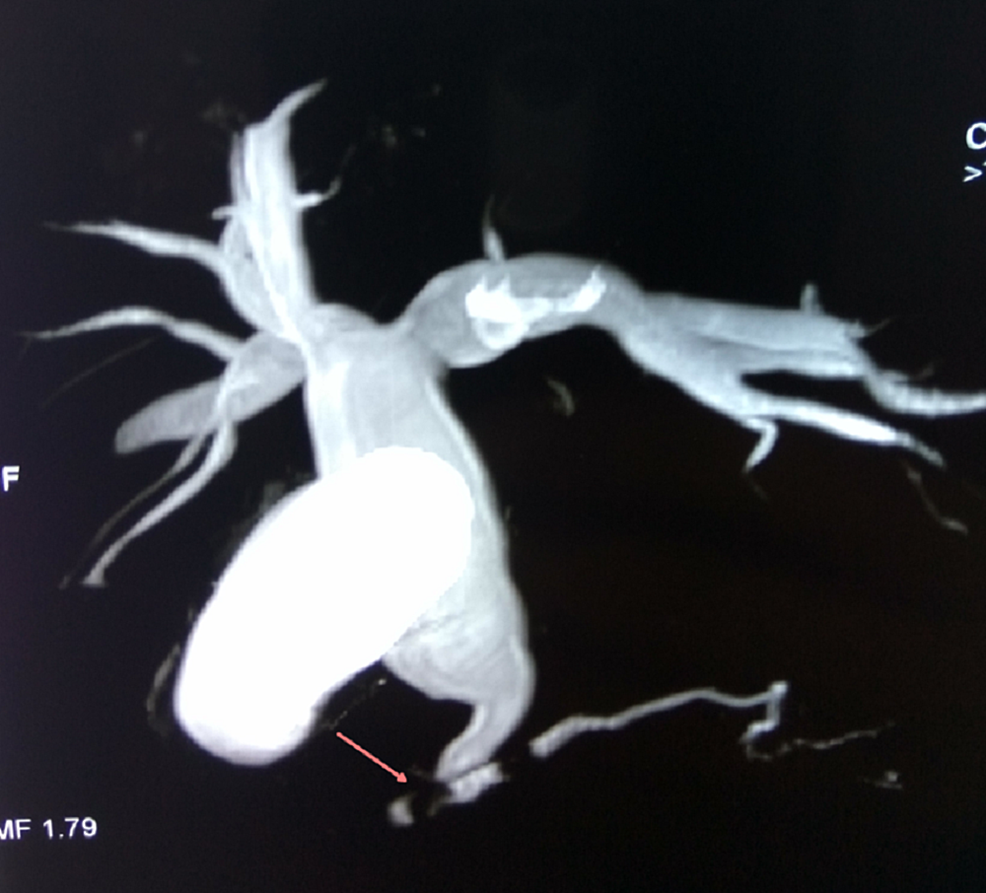

From www.researchgate.net

Choledocal cyst (type Ic). 3D MRCP Maximun Intensity Projection Type Ic Choledochal Cyst Type i cysts are a dilatation of the extrahepatic bile duct. A choledochal cyst (cc) or biliary cyst is a congenital or acquired anomaly affecting the biliary tree. Characterized by fusiform dilation of the extrahepatic bile duct. Biliary cysts, also termed choledochal malformations, are cystic dilations that may occur singly or in multiples throughout. Choledochal cyst is a congenital cystic. Type Ic Choledochal Cyst.